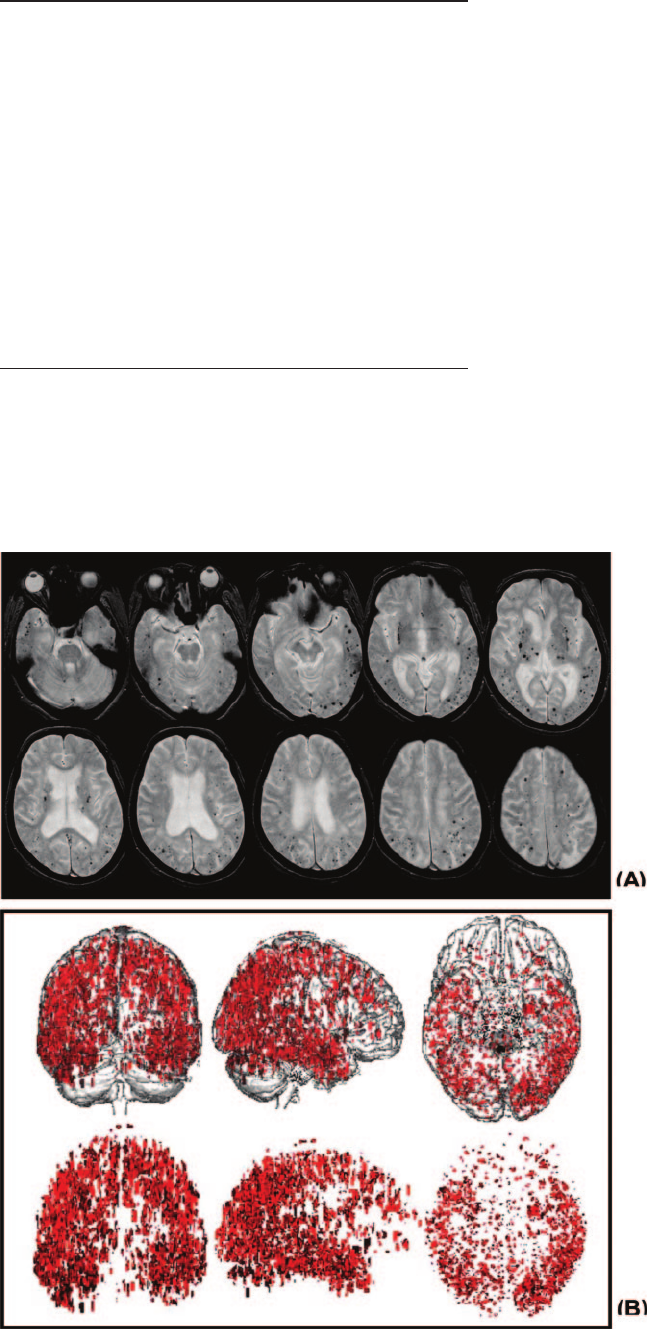

A, An illustration of GE-MRI of a typical

patient who showed severe cortical MBs

predominantly in temoporoparietal area.

B, To illustrate the distribution of cortical

MBs, cortical MBs on axial scans of

GE-MRI from all patients were depicted

on the glass brain of a single subject.

Frequency and Distribution of MBs

Details of demographic and MRI findings of the patients are

presented in Table 1. MBs occurred in 73 of 86 (84.9%)

patients. The total number of MBs in the 73 patients was 4147

and the number of MBs per patient ranged from 1 to 613 with

a median number of 13. MBs were most commonly distrib-

uted in the cortex (Table 2), and the cortical MBs were most

pronounced in the temporoparietal area (Figure).